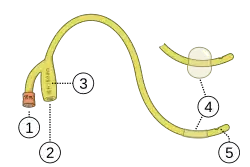

Las sondas de Foley son tubos flexibles, generalmente de látex, que en la cateterización urinaria se pasan a través de la uretra y hacia el interior de la vejiga. Este procedimiento se realiza por varios objetivos, uno de ellos es para obtener una muestra de orina libre de gérmenes, o bien para ayudar a aliviar una vejiga distendida.[1] Quedan retenidos por medio de un globo en la extremidad del catéter que se infla con agua estéril.[2] Los globos vienen típicamente en dos tamaños diferentes, 5 cm³ y 30 cm³.[3]

El tamaño relativo de un catéter de Foley se describe usando la escala de Charrière (Ch) o escala francesa (F). Los catéteres de Foley más comunes tienen típicamente un rango que va de 10 F a 28 F.[4] 1 F es equivalente a un tercio de milímetro, es decir, 0,33 mm = 0.013" = 1/77" de diámetro. Así, el tamaño en unidades de Charrière es más o menos igual a la circunferencia del catéter en milímetros.